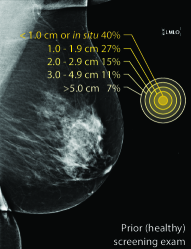

Masking refers to the phenomenon in which a tumor is hidden by the surrounding breast tissue, causing the cancer to be difficult or even impossible to discern with regular mammography, as seen in Figure 2. Masking can also result in large invasive cancers111We define large invasive cancers as those confirmed to have spread and be 2cm at time of diagnosis. – a small cancer may be difficult to discern in certain images, allowing it to grow to a more lethal size. Masking is correlated with breast density, as it has been shown that cancer in dense breasts is more likely to be missed during screening [5, 6, 7]. Density can be subjectively assessed by radiologists via the BI-RADS density standard (ACR) [8, 9], or measured by automated tools such as Libra [10]. These density measurements, however, do not perfectly correlate with masking potential. Radiologists consider the distribution and pattern of tissue when assessing masking potential, and have called for automated methods to assess the masking effect [11]. Until now, the question of exactly how masking potential should be quantified remains an open one, although some subjective notion has been added to certain categories of the most recent edition of BI-RADS density [12].

In this work, we introduce the CSAW-M dataset – a collection of over 10,000 mammographic images and associated masking assessments from experts. The assessments were graded by radiologists according to 8 levels of masking potential, as depicted in Figure 1, from easily assessed mammograms with low-masking potential (level 1) to difficult-to-assess examples with high-masking potential (level 8). This data can be used to train models capable of predicting masking potential from mammographic images in an ordinal classification setting.

| Large invasive cancer | Same cancer, likely masked | Tumor size & frequency | |

The goal of the annotation procedure was to label each image with expert assessments of masking potential. Masking was quantized into 8 bins, or levels, as depicted in Figure 1, for the public training and test sets. Images in the private test set are fully sorted according to masking. Individually sorted examples provide a more granular assessment, but at the cost of increased annotation time. We opted for fine granularity on the private test set because (1) it allows for a more fine-grained assessment, and (2) it allowed us to identify robust initial bins555We use “bin” and “level” interchangeably to denote collections of images with similar masking potential. for the 8 masking levels in the public training/test sets. To represent the initial bins, we chose images personalized to each radiologist, but with highest agreement among the other experts. The benefit to this approach is that the starting point respects subjective assessments while at the same time choosing representative examples for each masking level.